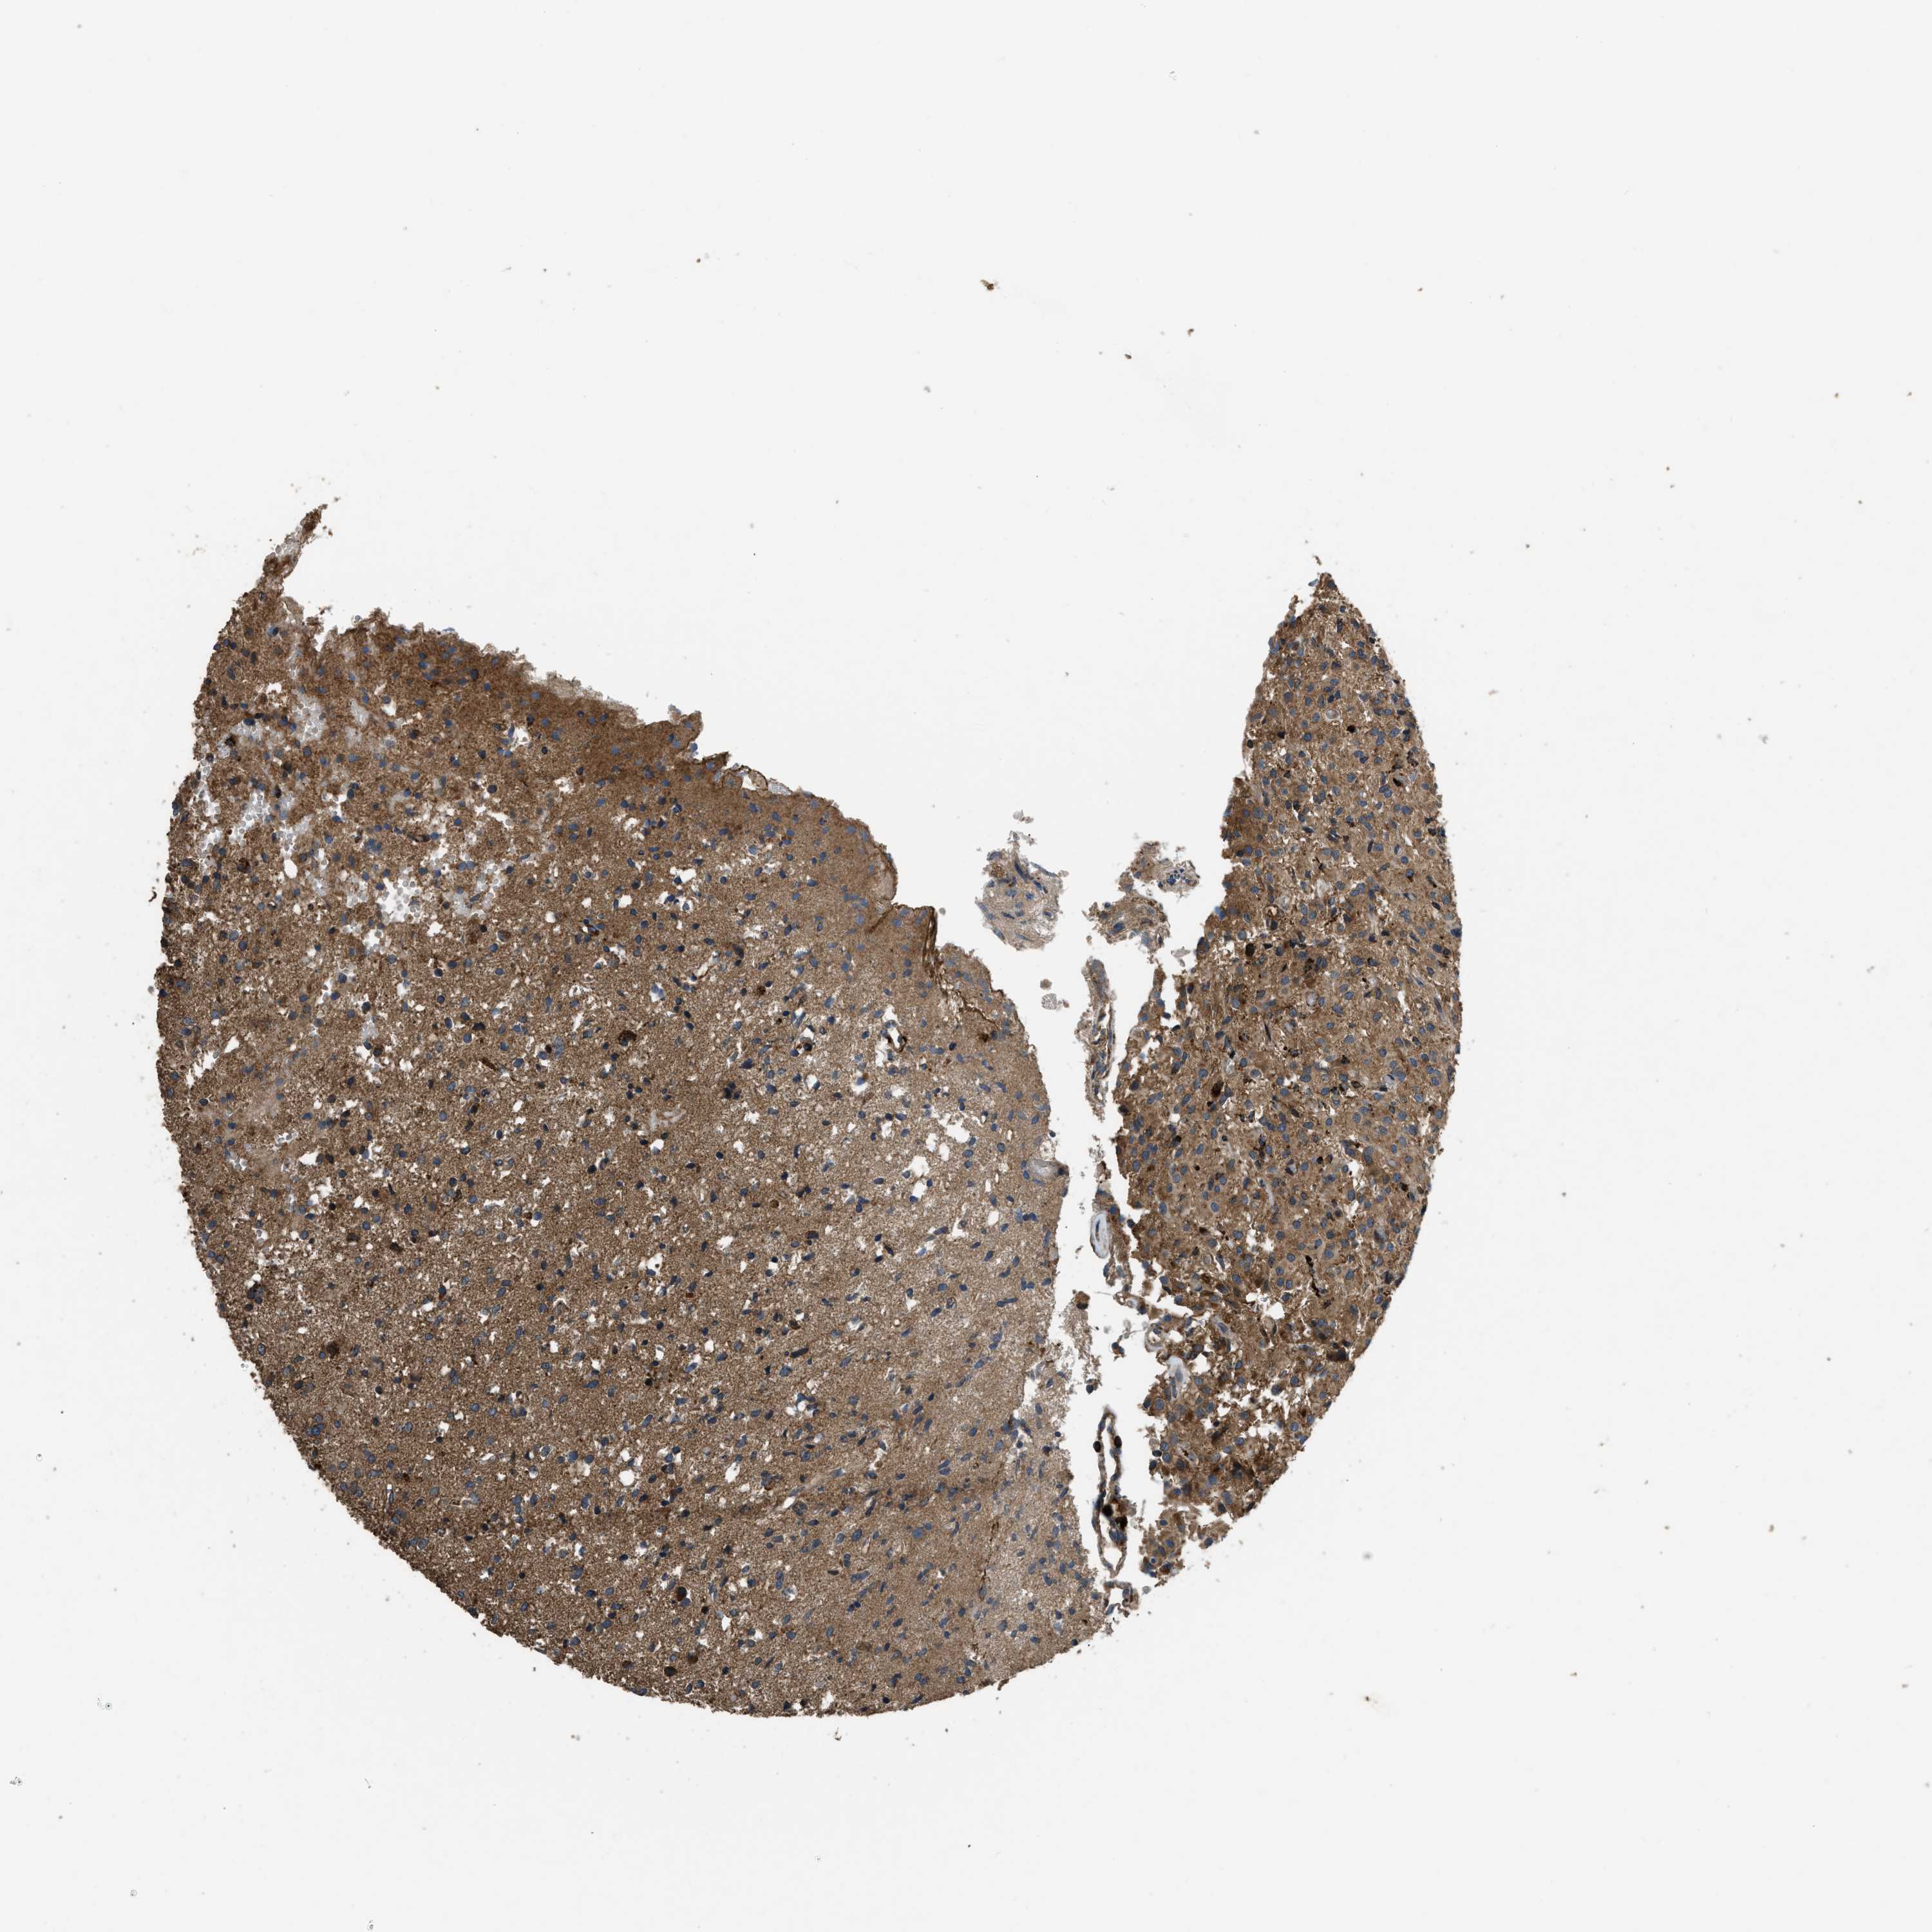

GLIOMA - Protein expressioni

A mouse-over function shows sample information and annotation data. Click on an image to view it in a full screen mode. Samples can be filtered based on level of antibody staining by selecting one or several of the following categories: high, medium, low and not detected. The assay and annotation is described here.

Note that samples used for immunohistochemistry by the Human Protein Atlas do not correspond to samples in the TCGA dataset.

Antibody stainingi

Antibody staining in the annotated cell types in the current human tissue is reported as not detected, low, medium, or high, based on conventional immunohistochemistry profiling in selected tissues. This score is based on the combination of the staining intensity and fraction of stained cells.

Each image is clickable and will lead to virtual microscopy that enables deeper exploration of all samples and also displays staining intensity scores, fraction scores and subcellular localization as well as patient and tissue information for each sample.

Antibody HPA025226

Antibody CAB019296

Staining

High

Medium

Low

Not detected

Intensity

Strong

Moderate

Weak

Negative

Quantity

>75%

75%-25%

<25%

None

Location

Nuclear

Cytoplasmic/membranous

Cytoplasmic/membranous,nuclear

Glioma, malignant, High grade

Glioma, malignant, Low grade